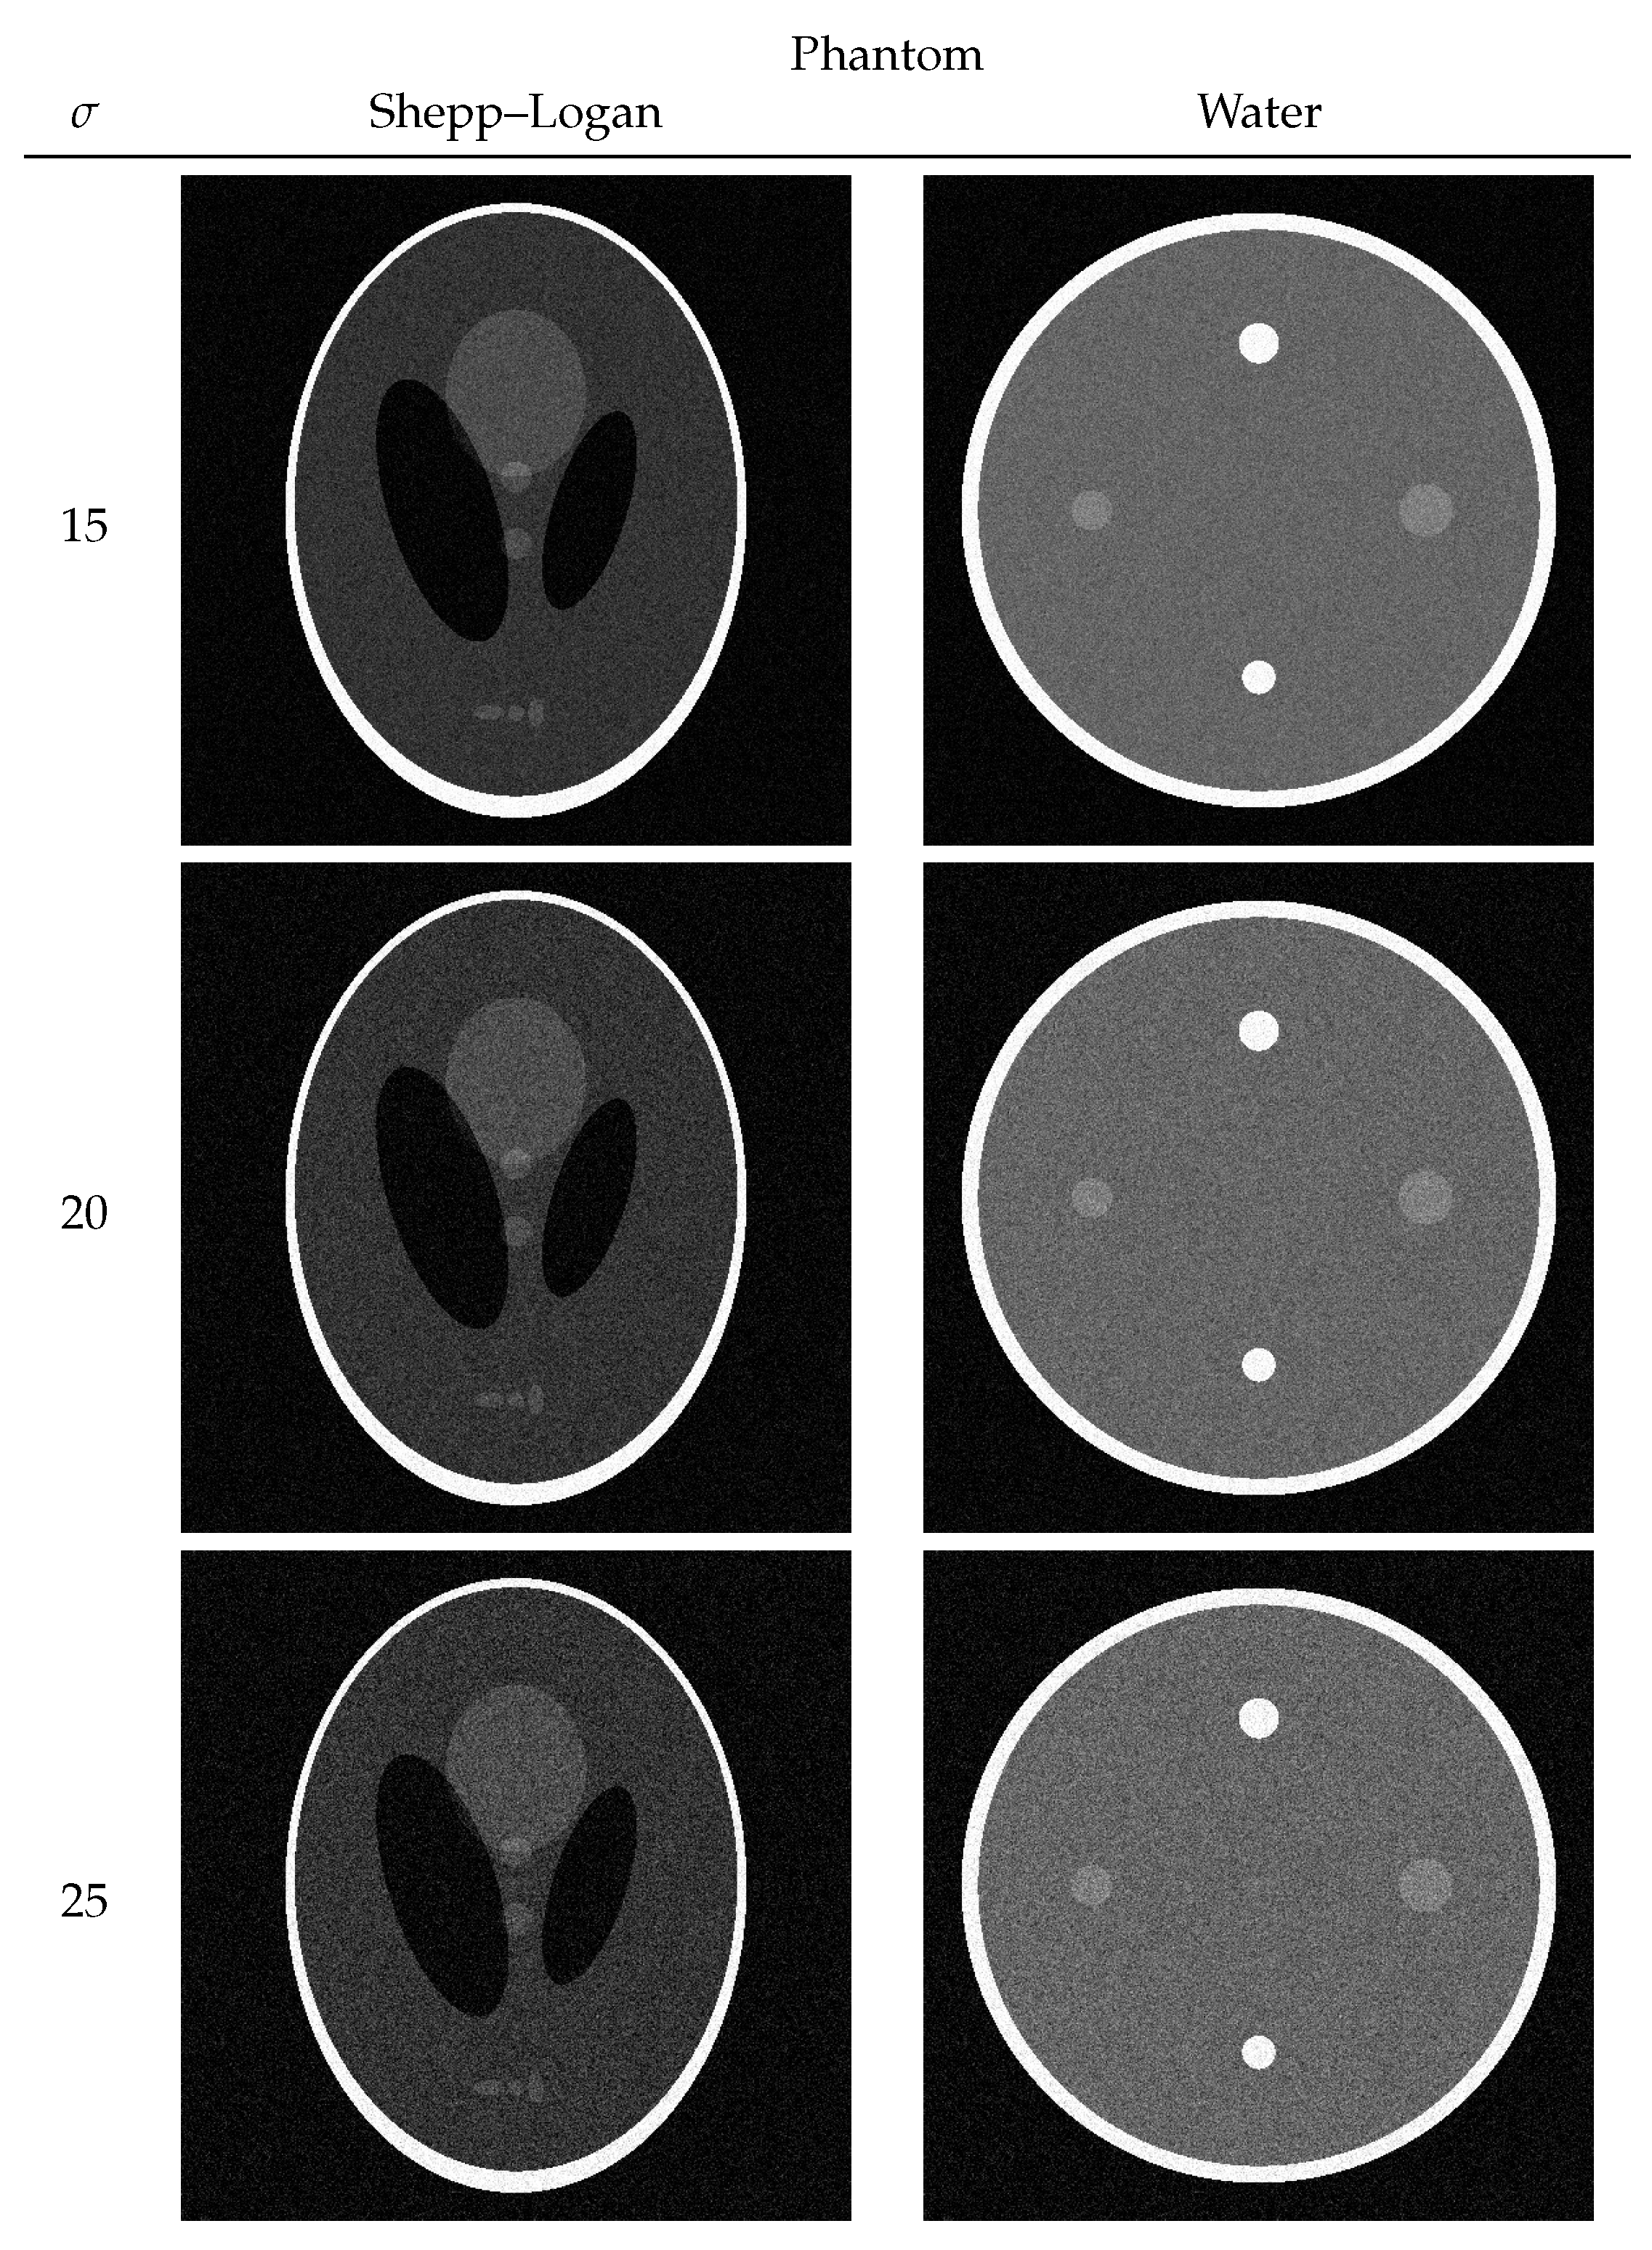

3.1. Numerical Phantom